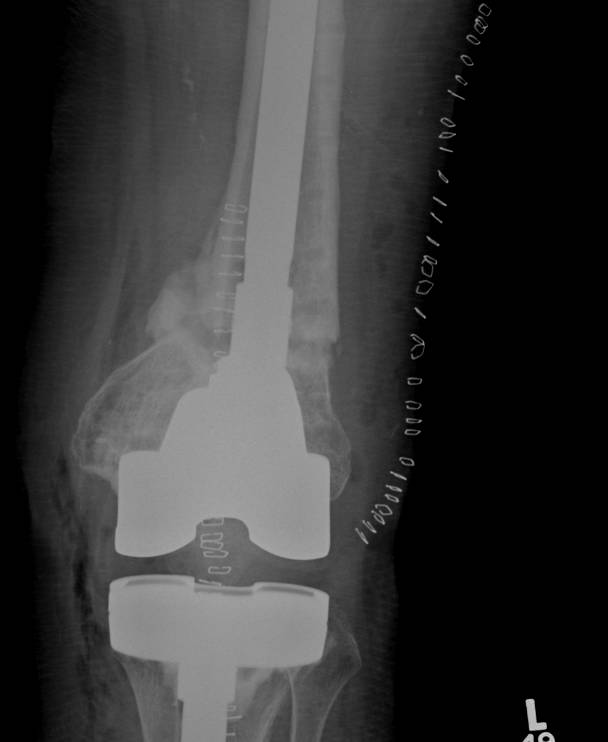

3.  Anterograde nail

Indications

- sufficient bone above implant for distal locking

Issues

- stress riser between femoral implant and nail

- must ensure correct alignment

TKR Femoral FractureTKR Femoral Nail APTKR Femoral Nail Lateral